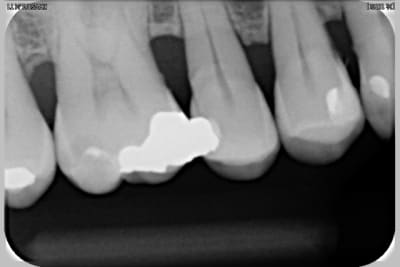

Pas de pano ? On n'a pas les même suivis , NP ( nouveau patient) = pano et radio complête.

Examen paro ? sondage et rétro ?

pour la dent 12 , il semble que ce soit lié avec la Cl-2, div-2 ( une des variante). Mais peut-être paro...on manque d'info. Pour le wax-up, c'est trop tôt.

Voir images

On peut y voir une remodelage osseux, de tartre, l'usure de la canine